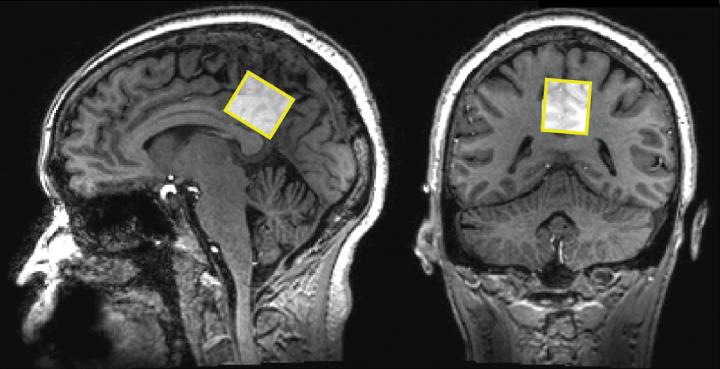

The researchers wanted to measure neurotransmitters and brain metabolites found in parts of the brain known to show changes in people with Alzheimer's disease: the anterior cingulate cortex and the posterior cingulate cortex. Both places fall in the part of the brain responsible for thinking and mood in the center midline that divides the brain into right and left hemispheres, with one location near the front of the head and the other near the back. Each MRS scan for a specific brain region with the 7-Tesla magnet took approximately 5-10 minutes to get sufficient resolution and signal strength of the chemical components in each of the brain locations.